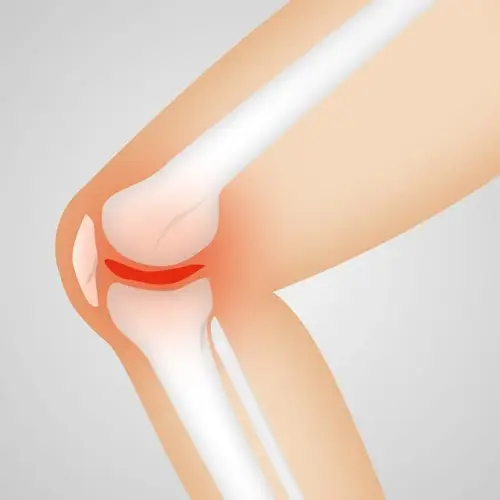

통풍의 가장 큰 특징은 갑자기 찾아오는 극심한 통증입니다. 많은 분들이 "바람만 스쳐도 아프다"고 표현할 만큼 고통스럽습니다. 특히 엄지발가락 관절에 통증이 집중되는 경우가 많은데, 요산염 결정이 관절에 쌓이며 염증 반응을 일으키기 때문입니다.

급성 통풍 발작은 보통 밤에 갑자기 시작되며, 주로 엄지발가락 관절에 극심한 통증과 붓기가 나타납니다. 이때 관절 부위가 붉게 달아오르고 열감이 동반되며, 걸을 수 없을 정도로 고통스럽습니다. 일부 환자는 발열과 오한을 호소하기도 합니다.

특히 만성 결절성 통풍 단계에서는 관절이 변형되고, 요산 결정이 피부 아래에 혹처럼 쌓여 통풍 결절이 생깁니다. 이러한 상태까지 진행되면 일상생활에 큰 지장을 주고, 신장에도 부담을 줍니다.